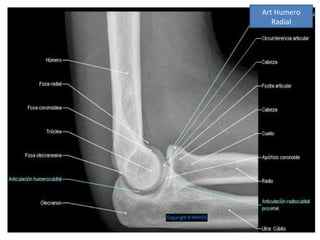

Art Humero

Radial

Articulación húmero-radial

Es de tipo condilartrosis.

Movimientos: Flexión-

extensión, rotación,

pronosupinación.

Superficies articulares:

Húmero: Cóndilo del

húmero (de forma esférica)

Radio: Carilla cóncava del

radio.